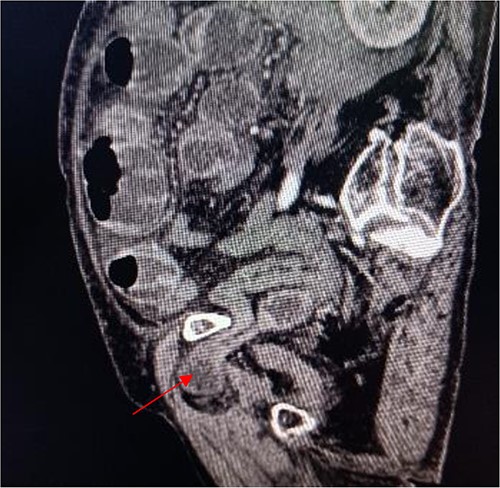

Tumor (indicated by black arrow) on the ascending colon observed during operation.

Laparoscopic exploratory laparotomy and obturator hernia repair were performed. A 4 × 4 cm thick hard tumor was observed in the ascending colon near the liver curve, involving serosa, and the ascending colon was partially blocked. A total of 80 cm away from ileocecum, the intestine entered from the right obturator hernia, causing obstruction and expansion of the proximal intestinal canal, congestion, and edema of the intestinal wall. We aspirated the ascites, loosened the adhesion around the obturator hernia ring, and returned the small intestine back into the abdominal cavity. It was observed that the intestinal wall of the hernia section was ~4 cm, necrotic, and broken, and the intestinal contents were flowing out, the intestinal defect was immediately closed, the abdominal cavity was flushed with normal saline, and the peritoneum at the obturator was intermittently sutured and repaired. A median abdominal incision of ~12 cm was used to cut each layer of the abdominal wall, enter the abdomen, protect the incision, lift out the intestine at the breach, place the aspirator in the intestinal lumen, aspirate large amount of intestinal contents, and temporarily close the breach. The abdominal and pelvic cavities were rinsed again with plenty of normal saline. With the consent of the patient’s family, a double-cavity ileostomy was successfully performed.